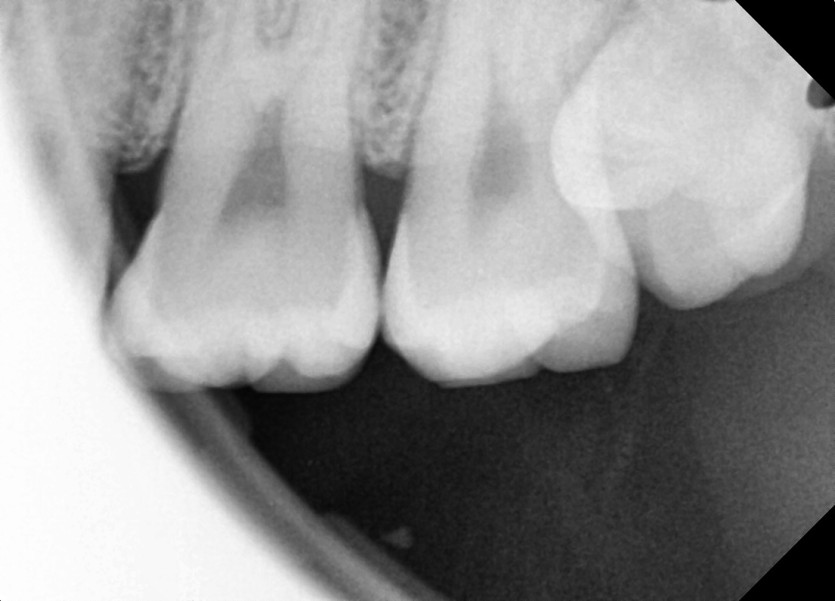

#28,38 사랑니 발치

구강 외과 전문의가 당일 발치했습니다.